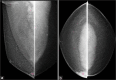

Most of male breast masses are benign with gynecomastia being the most common entity encountered. Primary male breast cancer accounts for less than 1% of the total number of breast cancer. Male breast can be affected by a variety of conditions affecting the female breast with less frequency due to the lack of hormonal influence and consequent glandular sub-development. Imaging features of male breast masses are quite similar to the female breast. Therefore, using the knowledge of the female breast and applying it may help in the diagnosis and management of male breast abnormalities. In this article, we aim to review a variety of unusual male breast masses. We discuss the demographics of male breast tumors, describe the diagnostic algorithm for evaluating male breast masses, and review the imaging features of rare breast masses and mimickers of male breast cancer.